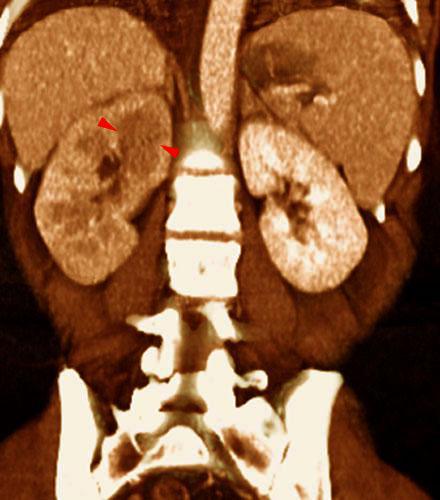

Obstrucción renal en duplicidad. Absceso renal